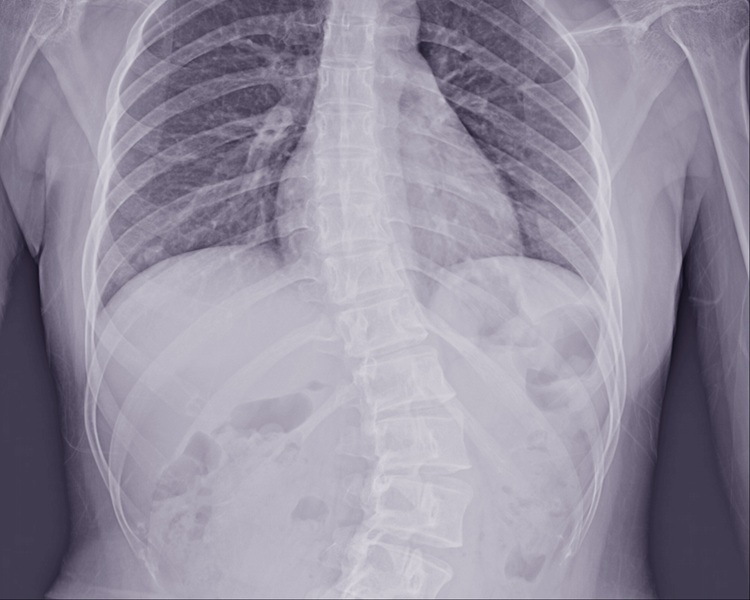

Scoliosis

Scoliosis is a sideways curvature of the spine that can cause uneven posture, back pain, and limited mobility. Whether mild or more severe, early detection and targeted treatment can help manage symptoms and prevent progression. Our experienced team offers posture correction, manual therapy, and tailored exercise programs to support spinal alignment and improve quality of life.